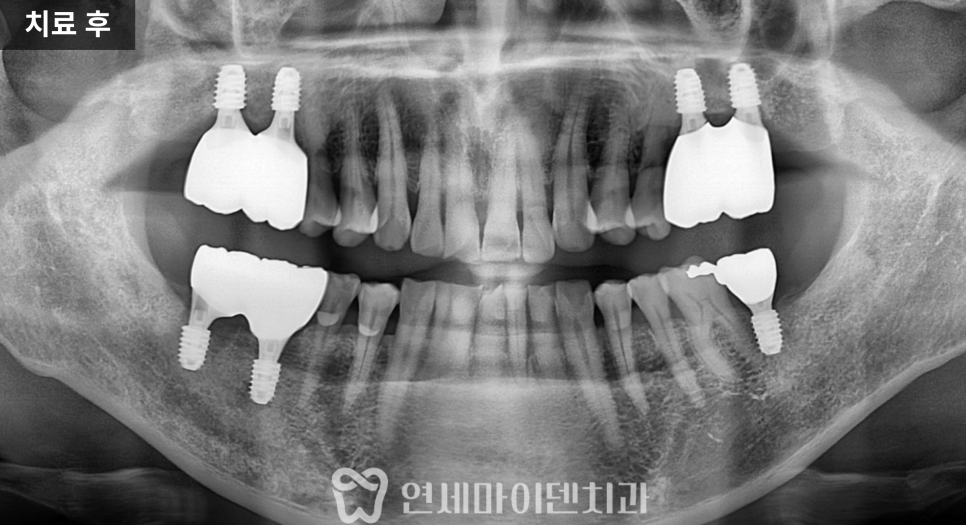

경과 관찰 후 보철 연결

수술 후에는 잇몸 회복 상태를

지속적으로 확인했습니다.

염증의 원인이 제거되면

잇몸은 비교적 빠르게 안정되는 경우가 많습니다.

3개월의 치유 기간을 거친 뒤

상부 구조를 연결하고

맞춤형 지대주를 형성한 후

보철을 완성했습니다.

이 시점부터 해당 부위로 식사가 가능해졌고

환자분의 생활 불편이 크게 줄었습니다.

이후 잇몸 회복을 확인하면서

보철까지 마무리했고

양쪽 어금니로 균형 있게

식사가 가능한 상태를 목표로 치료를 진행했습니다.

전반적인 잇몸 관리는

지속적으로 병행하며

보존 가능한 치아는

최대한 유지하는 방향

으로 이어졌습니다.